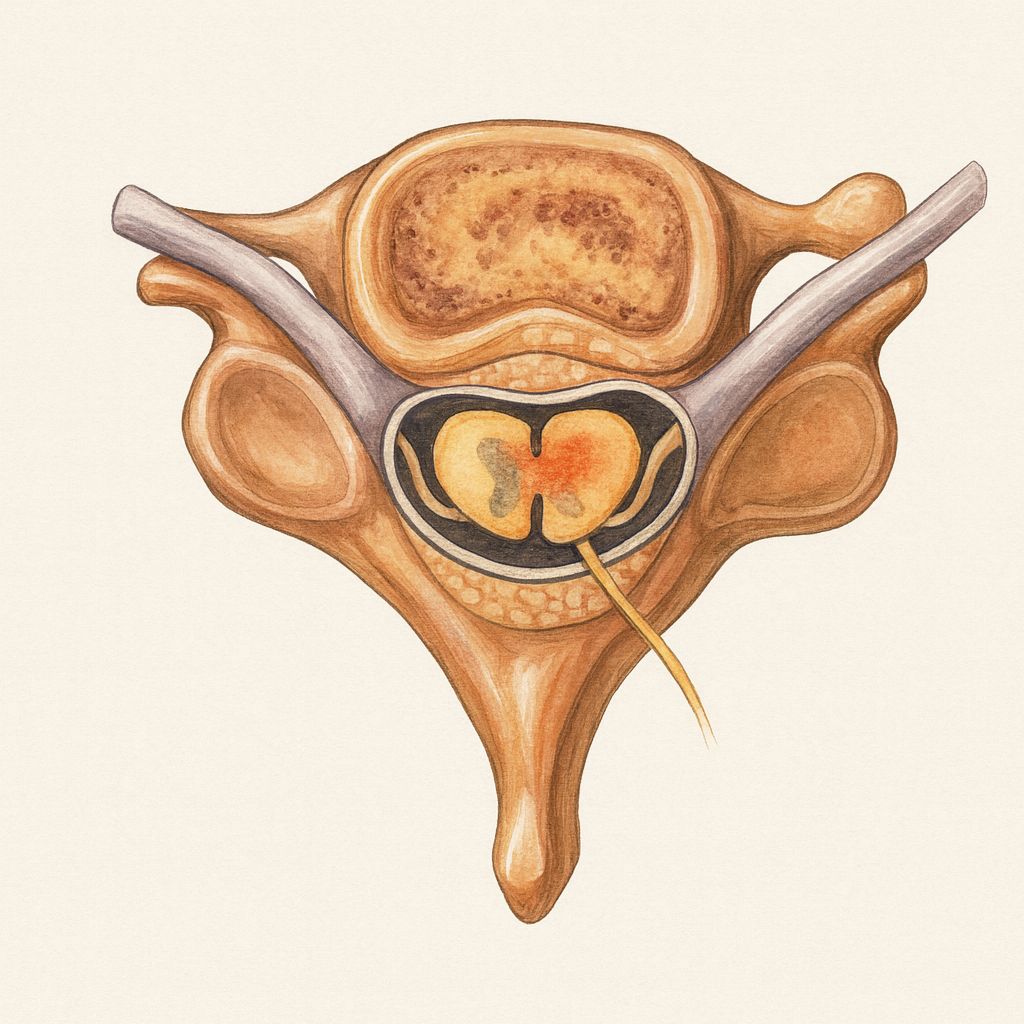

MRI of the lumbar spine demonstrates multilevel degenerative disc disease with a left paracentral L4–L5 disc-osteophyte complex causing L5 nerve root compression and moderate left L5–S1 foraminal stenosis.

- Lumbar spondylosis involves progressive degenerative changes affecting the intervertebral discs, facet joints, and ligamentum flavum.

- Disc degeneration leads to loss of disc height, annular bulging, and osteophyte formation at the vertebral endplates and facet joints.

- Foraminal stenosis from a combination of disc bulging, osteophytic overgrowth, facet joint hypertrophy, and ligamentum flavum thickening compresses the exiting nerve roots.

- Central canal stenosis may also contribute, particularly with large midline disc protrusions or diffuse degenerative hypertrophy, causing neurogenic claudication.

- Nerve root compression triggers a cascade of intraneural edema, demyelination, axonal injury, and dorsal root ganglion sensitization.

- Chronic compression activates inflammatory pathways (TNF-α, PGE2, nitric oxide) that sensitize nociceptors and produce neuropathic pain independent of ongoing mechanical compression.